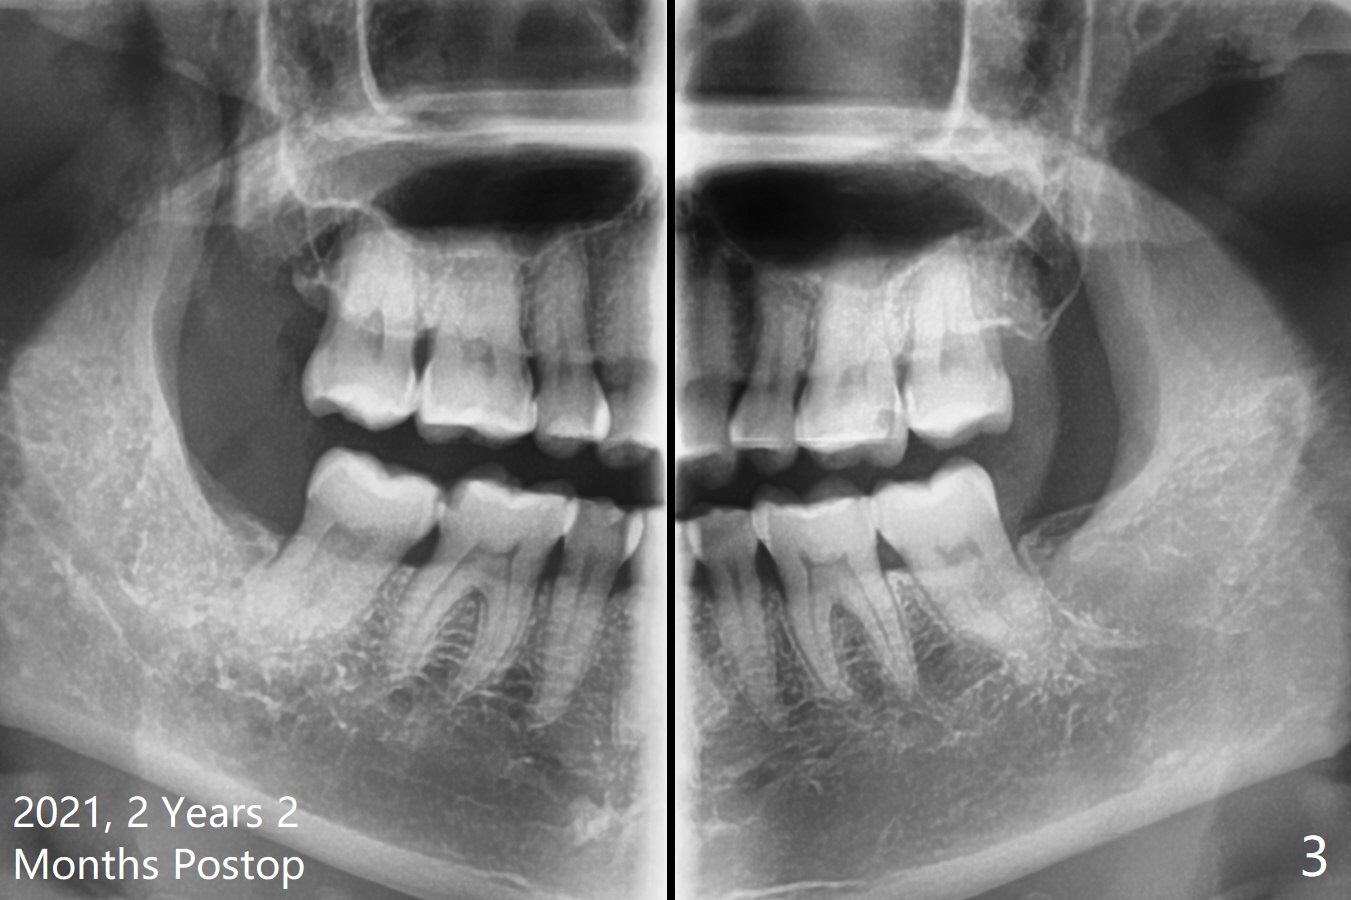

51岁女要求拔除#32(图一),劈牙两次,牙槽窝塞入胶原骨(Osteogen Plug),缝合,术后12天有不典型干槽症。术后2.5月第二,三磨牙之间牙槽嵴薄(图二:>),术后2年2个月#32牙槽窝密度高于#17(术后至少13年,图三)。